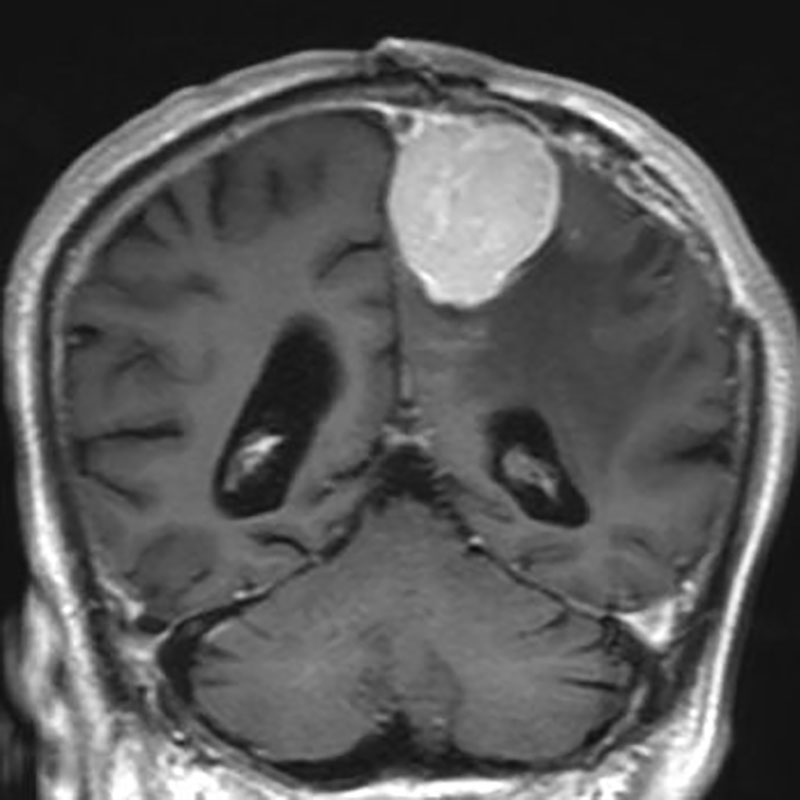

332

'22年9月

70代

円蓋部髄膜腫

頭蓋内腫瘍摘出術

No.’22_89 手術前1

No.’22_89 手術前2